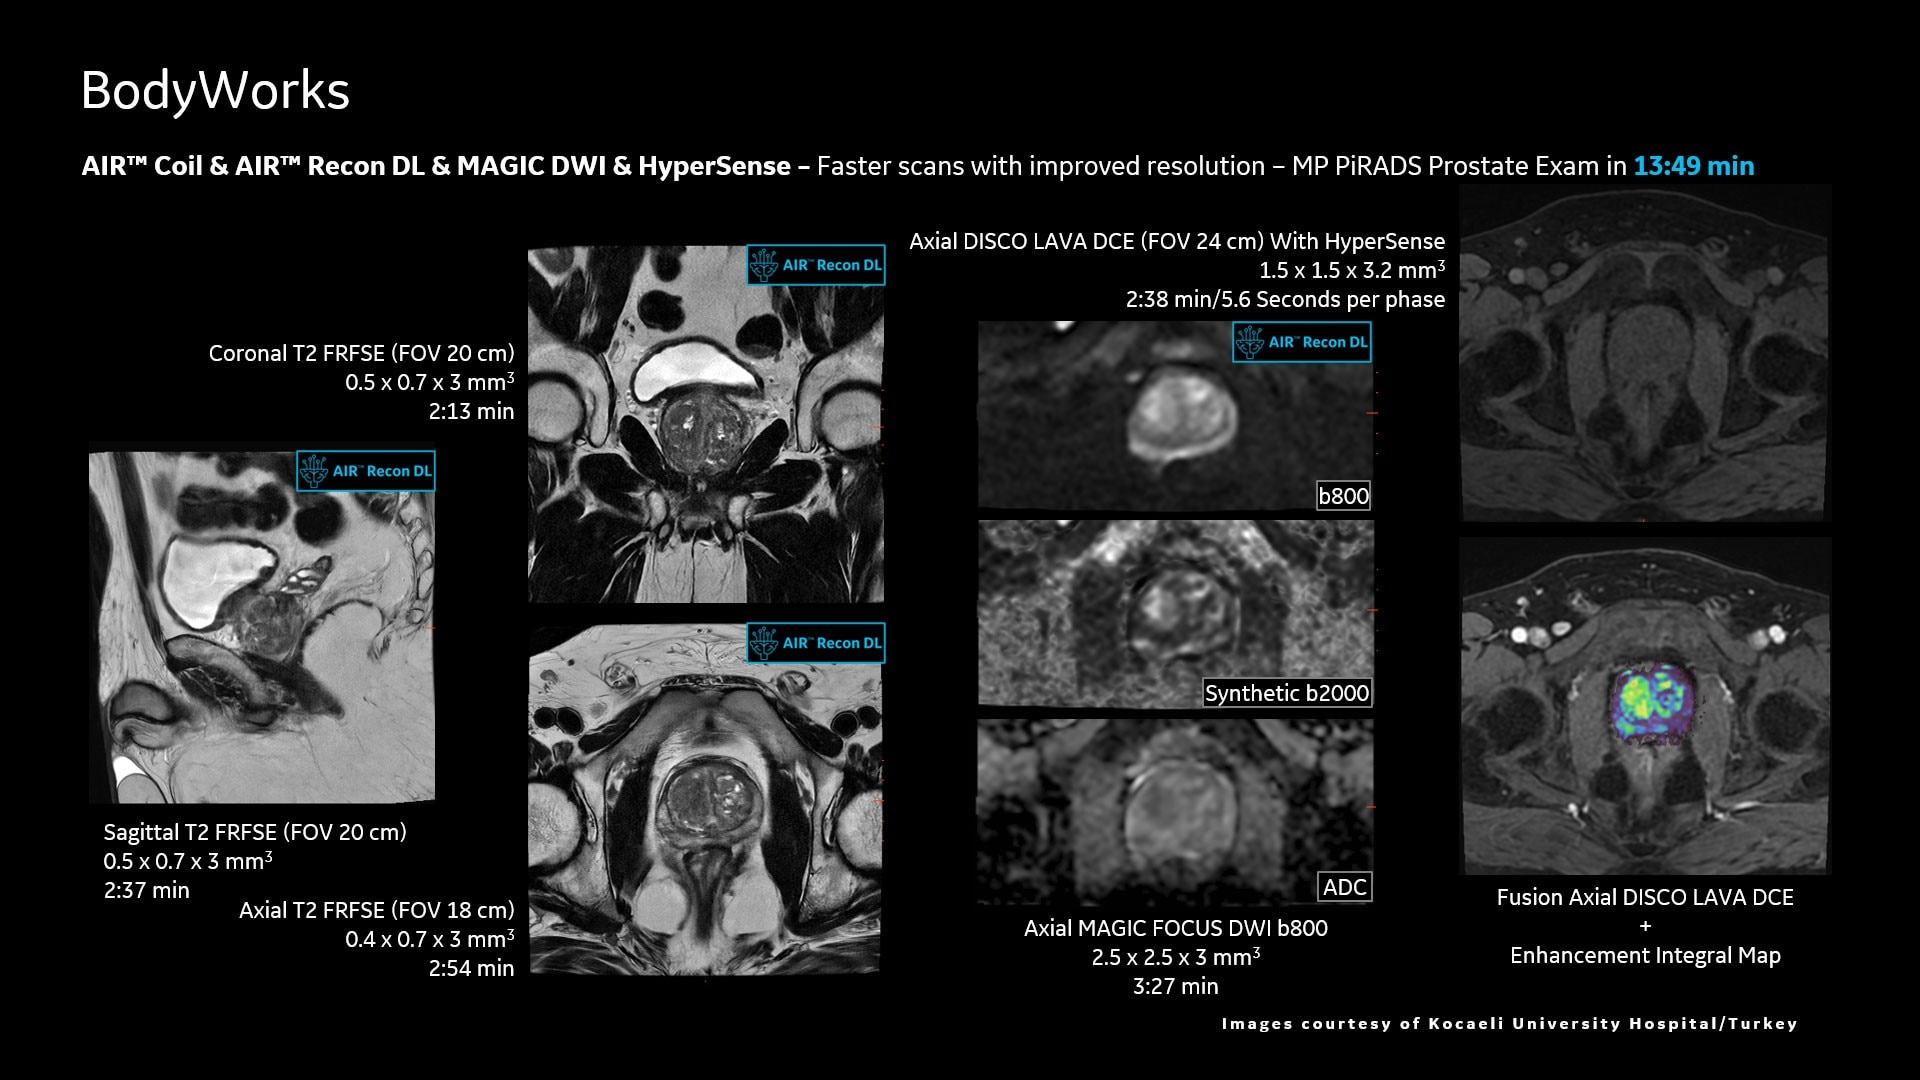

AIR™ Recon DL improves SNR and image sharpness, enabling shorter scan times

Up to 50% faster acquisition time with AIR™ Recon DL

Achieve a 25% efficiency gain with Ultra High Efficiency (UHE) gradient system. Fast, clear Total Digital Imaging (TDI) increases SNR by 25%. Improved IQ in 80% of cases without added time. Acquire higher SNR without a time penalty and get images virtually free of artifact with AIR™ Recon DL.***